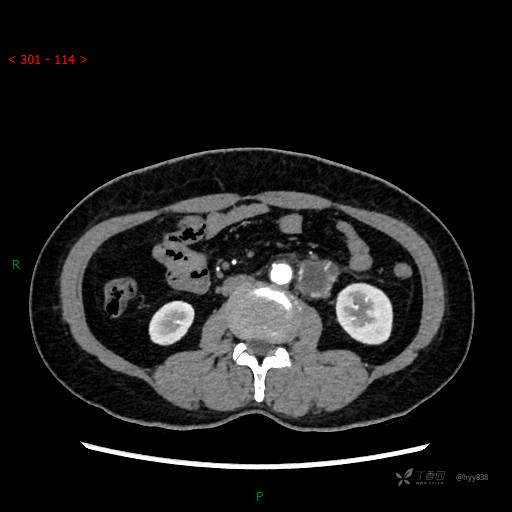

增强动脉期

静脉期